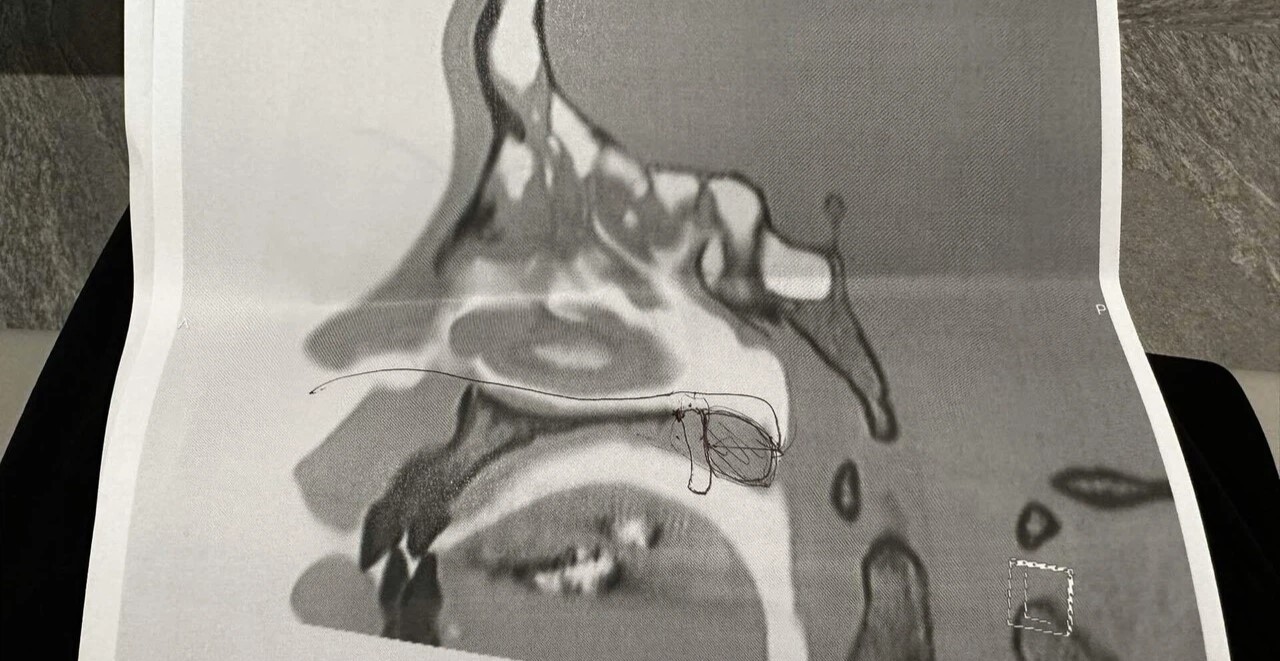

First of all, I was born without a sense of smell. Not because of some vague sensory issue, but for purely physical reasons:

From birth, the bone deep inside my nose was abnormally narrow—practically sealed shut. Because of that, oxygen can’t pass through, which means I can’t breathe through my nose, and scents can’t reach me either.

※ Following the tests at the major hospital, my condition was provisionally labeled as “congenital choanal atresia.”

In other words: I was born with the back of my nasal passage blocked, so I can’t breathe through my nose—and along with that, I have no sense of smell.

My condition stems from the fact that, for some reason, I was born without a connection between my nose and mouth. Which means air could never pass through my nose.

They cut through the hardened tissue in the depths of my nose—toughened from years of failed childhood surgeries—scraped together nasal mucosa to guard against it sealing shut again, and inserted tubes for several days.